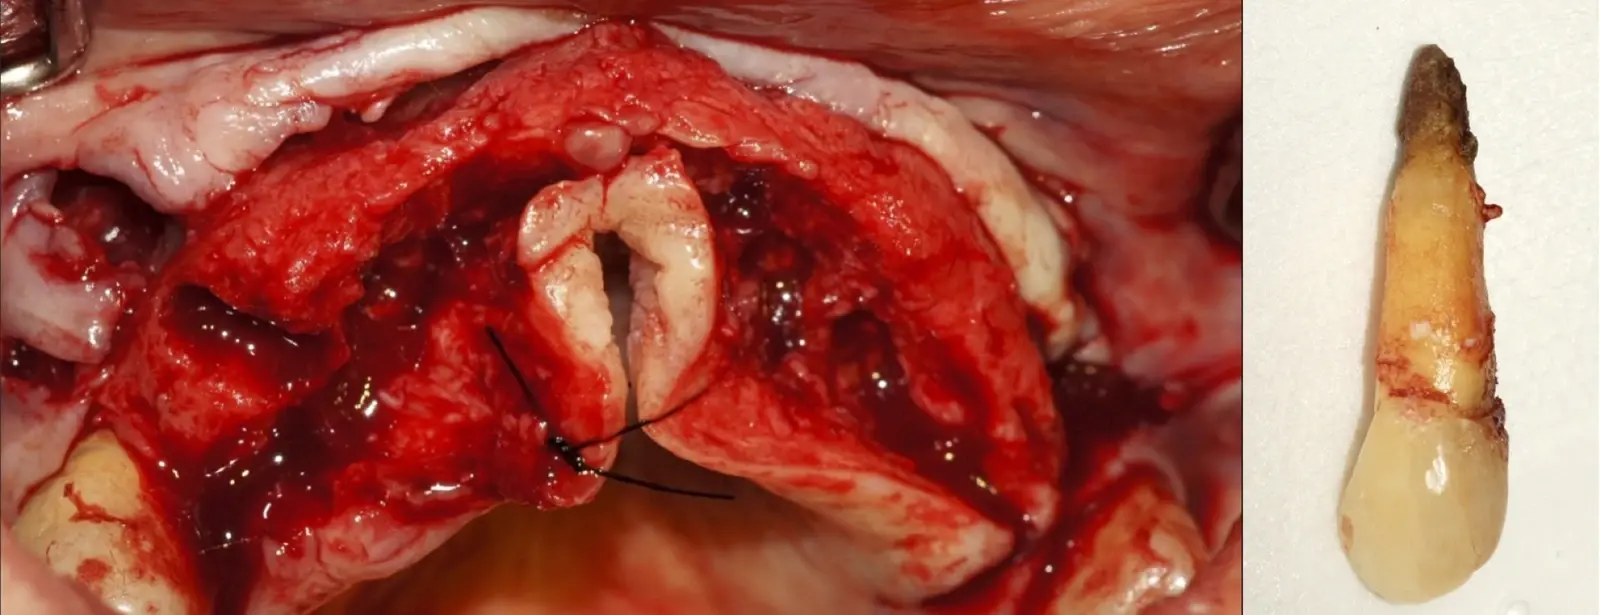

El origen puede ser bacteriano (colonias bacterianas persistentes4, patología periodontal asociada5, reinfecciones por falta de sellado coronal), mecánico (preparación deficiente, fractura de instrumentos, fracturas radiculares6, extravasación de material de obturación7 con ó sin compromiso de estructuras vecinas) y anatómico (conductos accesorios poco permeables o calcificados)8 (Figuras 1 - 4).

Figura 1. Tomografía cone beam en la que se observa la pieza 1.4 aparentemente normal, sin signos de patologías.

Figura 2. Exodoncia de la pieza 1.4 indicada como parte de una planificación de implantes dentales.

Figura 3. Concrescencia a nivel apical en la pieza extraída.

Figura 4. El mayor aumento de la concrescencia es observa a nivel apical.